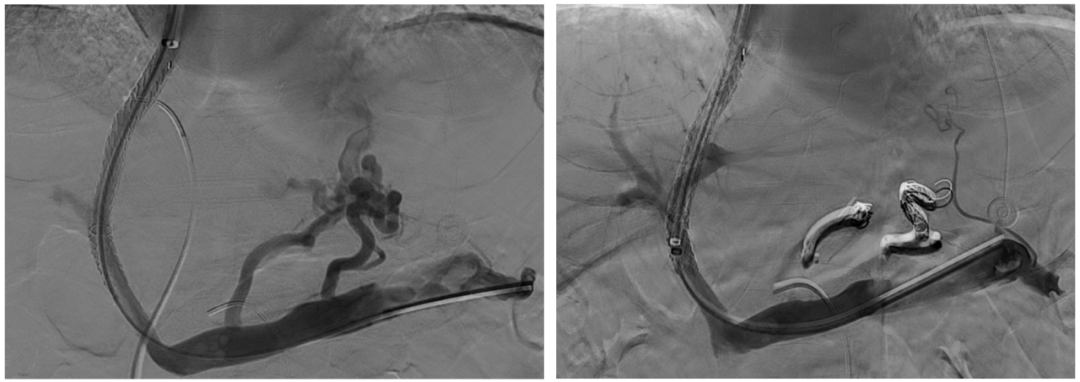

超选至肠系膜下静脉异常分流道,予以栓塞18mm的Amplatzer vascular plug及适量25%生物胶,造影示异常分流道消失

异常分流道栓塞后,再次行门静脉造影,血流呈向肝状态,食管胃底曲张静脉较前更显著,微导管超选至曲张的胃冠状静脉,予以弹簧圈及25%生物胶栓塞,造影示曲张静脉消失,肝内门脉显影较术前显著改善

仔细评估术前CT可知,该患者的异常分流道的出口并不引流至肾上腺静脉,故难以通过常规BRTO途径栓塞,因而对于该患者团队仔细评估后决定采用TIPS联合异常分流道近端栓塞的方法。既往对于此类粗大分流道,无论是单纯使用可控弹簧圈或是弹簧圈联合组织胶水都存在栓塞效率或是安全性的不足,该患者使用血管塞封堵减缓血流后,在血管塞细密的网孔阻隔下能够有效防止补充栓塞的组织胶逃逸,进而获得良好的栓塞效果及效率。